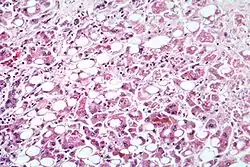

| Alcoholic hepatitis as seen with a microscope, showing fatty changes (white circles), remnants of dead liver cells, and Mallory bodies (twisted-rope shaped inclusions within some liver cells). (H&E stain) | |

Excessive alcohol consumption is a significant cause of hepatitis and is the most common cause of cirrhosis in the U.S.[34] Alcoholic hepatitis is within the spectrum of alcoholic liver disease. This ranges in order of severity and reversibility from alcoholic steatosis (least severe, most reversible), alcoholic hepatitis, cirrhosis, and liver cancer (most severe, least reversible).[34] Hepatitis usually develops over years-long exposure to alcohol, occurring in 10 to 20% of alcoholics.[37] The most important risk factors for the development of alcoholic hepatitis are quantity and duration of alcohol intake.[37] Long-term alcohol intake in excess of 80 grams of alcohol a day in men and 40 grams a day in women is associated with development of alcoholic hepatitis (1 beer or 4 ounces of wine is equivalent to 12g of alcohol).[34] Alcoholic hepatitis can vary from asymptomatic hepatomegaly (enlarged liver) to symptoms of acute or chronic hepatitis to liver failure.[34]

Steatohepatitis is seen in both alcoholic and non-alcoholic liver disease and is the culmination of a cascade of events that began with injury. In the case of non-alcoholic steatohepatitis, this cascade is initiated by changes in metabolism associated with obesity, insulin resistance, and lipid dysregulation.[66][67] In alcoholic hepatitis, chronic excess alcohol use is the culprit.[68] Though the inciting event may differ, the progression of events is similar and begins with accumulation of free fatty acids (FFA) and their breakdown products in the liver cells in a process called steatosis.[66][67][68] This initially reversible process overwhelms the hepatocyte's ability to maintain lipid homeostasis leading to a toxic effect as fat molecules accumulate and are broken down in the setting of an oxidative stress response.[66][67][68] Over time, this abnormal lipid deposition triggers the immune system via toll-like receptor 4 (TLR4) resulting in the production of inflammatory cytokines such as TNF that cause liver cell injury and death.[66][67][68] These events mark the transition to steatohepatitis and in the setting of chronic injury, fibrosis eventually develops setting up events that lead to cirrhosis and hepatocellular carcinoma.[66] Microscopically, changes that can be seen include steatosis with large and swollen hepatocytes (ballooning), evidence of cellular injury and cell death (apoptosis, necrosis), evidence of inflammation in particular in zone 3 of the liver, variable degrees of fibrosis and Mallory bodies.[66][69][70]

Liver biopsies show identical findings in patients with ASH and NASH, specifically, the presence of polymorphonuclear infiltration, hepatocyte necrosis and apoptosis in the form of ballooning degeneration, Mallory bodies, and fibrosis around veins and sinuses.[34]